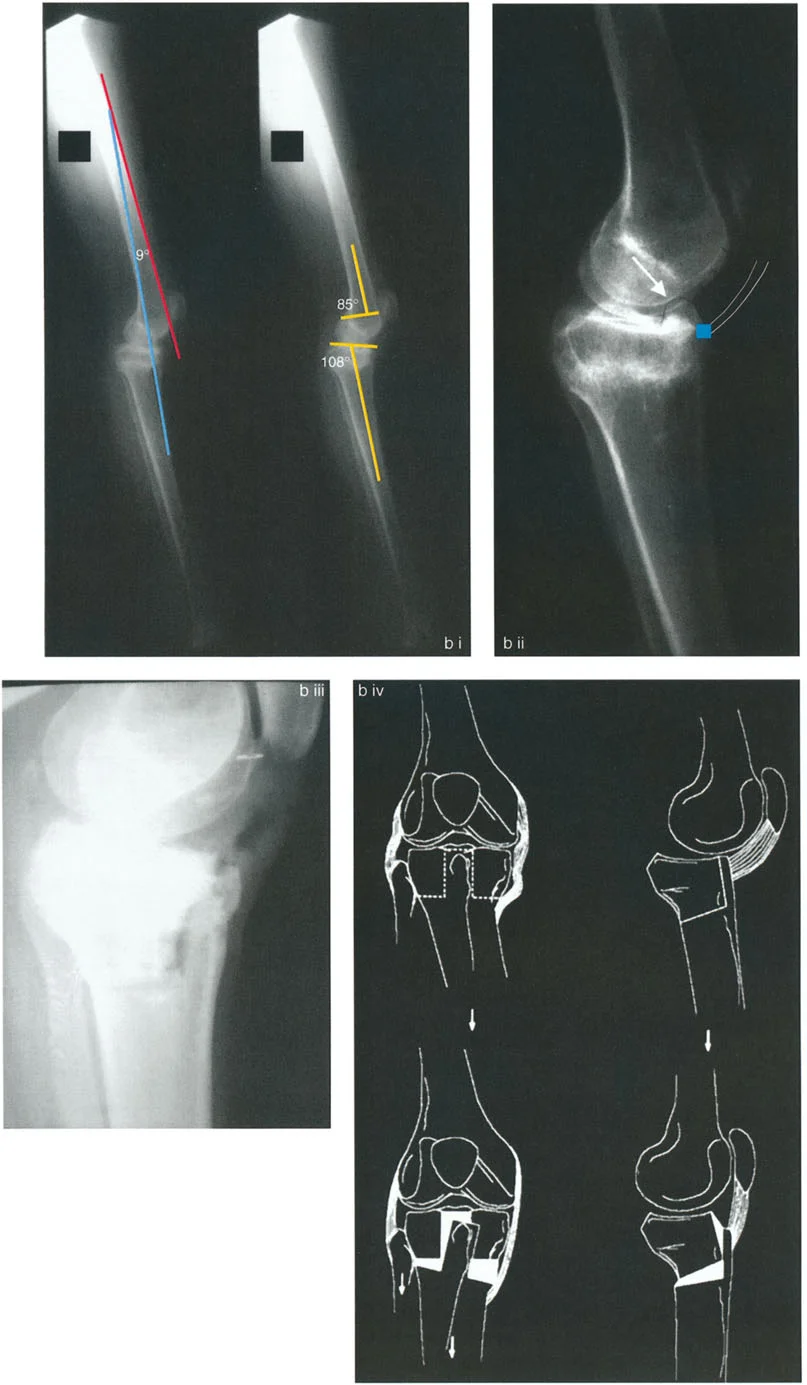

أنواع تشوهات الركبة السهمية الأسباب وعوامل الخطر

تظهر تشوهات المستوى السهمي حول الركبة عادة إما على شكل تقوس أمامي (Procurvatum) أو تقوس خلفي (Recurvatum). من الضروري التفريق بين التشوه العظمي والتقلص في الأنسجة الرخوة، على الرغم من أن التشوهات العظمية طويلة الأمد ستؤدي حتماً إلى تكيفات ثانوية في الأنسجة الرخوة.

التقوس الأمامي (Procurvatum) في الفخذ

ينتج التقوس الأمامي في الجزء البعيد من عظم الفخذ عادة عن فقدان تعويضي في قدرة الركبة على التمدد الكامل، أو اندفاع تقوسي ثانوي أثناء مرحلة الوقوف في المشي. نظراً لأن الجزء البعيد من عظم الفخذ ينحني للأمام، فإن خط المفصل يميل، مما يجبر عظم الظنبوب على فرط الاستقامة ببساطة للسماح للمريض بالوقوف بشكل مستقيم مع قدم مستوية.

عند تصحيح تشوه التقوس الأمامي، يجب على الجراح حساب مركز دوران الانحراف (CORA) بعناية. غالباً ما يكون التشوه قريباً جداً من المفصل، مما يجعل تثبيت العظم بعد القطع أمراً صعباً.

على سبيل المثال، قد يحتاج المريض الذي يعاني من تقوس أمامي شديد في الفخذ وتشوه تعويضي في الظنبوب القريب (مثل زاوية PPTA تبلغ 88 درجة و10 درجات من فرط الاستقامة السريري) إلى نهج متعدد المستويات على مراحل لاستعادة الحركة الطبيعية:

- تصحيح الفخذ: يتم إجراء قطع عظمي على شكل إسفين إغلاق أو إسفين فتح في الفخذ عند نقطة CORA. غالباً ما يتم تثبيت هذا بإبرة نخاعية (IMN) أو صفيحة تثبيت قوية.

- تصحيح الظنبوب: قد تتضمن عملية ثانوية قطع عظمي أسفل الحدبة الظنبوبية لتصحيح التشوه التعويضي في الجزء القريب من الظنبوب.

- نقل الرضفة: إذا كان هناك انخفاض ثانوي في الرضفة (غالباً بسبب ميكانيكا متغيرة طويلة الأمد أو جراحات سابقة)، يمكن نقل الرضفة للأعلى باستخدام مثبت خارجي (مثل جهاز إليزاروف أو إطار تايلور الفراغي) لاستعادة التوتر الطبيعي لآلية الباسطة.

تُظهر الصورة تشوه التقوس الأمامي في عظم الفخذ وكيف يؤثر على محاذاة الركبة، مما يستدعي تدخلاً جراحياً دقيقاً.

التقوس الخلفي (Recurvatum) وفرط استقامة الركبة

التقوس الخلفي في الجزء القريب من الظنبوب هو تشوه صعب بشكل فريد. على عكس الانحرافات الزاوية البسيطة، غالباً ما يؤدي التقوس الخلفي في الظنبوب القريب إلى خلع جزئي حقيقي خلفي للركبة.

عندما تميل هضبة الظنبوب إلى الخلف (مما يؤدي إلى زاوية PPTA عالية بشكل غير طبيعي، على سبيل المثال 95 درجة إلى 105 درجات)، ينعكس الميل التشريحي. يميل عظم الفخذ إلى الانزلاق للأمام على هذا الميل المعكوس، أو على العكس، ينخلع الظنبوب جزئياً إلى الخلف بالنسبة لقمة الفخذ. يخلق هذا عدم استقرار عميقاً، وعلامة سحب خلفي إيجابية، وآلاماً شديدة في الركبة الأمامية بسبب زيادة التحميل على آلية الباسطة.

دور الحدبة الظنبوبية في التخطيط لقطع العظم

عند التخطيط لقطع العظم لتصحيح التقوس الخلفي في الظنبوب، فإن موقع القطع العظمي بالنسبة للحدبة الظنبوبية هو القرار الأكثر أهمية الذي سيتخذه الجراح. فالنتائج الميكانيكية الحيوية لهذا الاختيار تحدد ما إذا كان خلع الركبة الجزئي سيتم تقليله أو تفاقمه بشكل كارثي.

قطع العظم فوق الحدبة الظنبوبية (النهج المفضل)

عندما يوجد تشوه تقوس خلفي مع وجود الحدبة الظنبوبية بالقرب من خط المفصل، فإن قطع العظم على شكل إسفين فتح فوق الحدبة الظنبوبية يكون مفيداً للغاية ويمثل المعيار الذهبي في مبادئ بالي لإعادة البناء.

- آلية العمل: يؤدي فتح إسفين عند هذا المستوى المحدد إلى تصحيح محاذاة العظم التقوسية، واستعادة زاوية PPTA الطبيعية (81-84 درجة) مباشرة.

- تقليل المفصل غير المباشر: نظراً لأن الحدبة الظنبوبية تبقى على الجزء البعيد من قطع العظم، فإن فتح الإسفين للأمام يسحب وتر الرضفة جسدياً. يعمل هذا الشد كحزام تقليل داخلي، يسحب كامل ساق الظنبوب وهضبة الظنبوب للأمام، وبالتالي يقلل بشكل غير مباشر الخلع الجزئي الخلفي للمفصل الظنبوبي الفخذي.

- منع انخفاض الرضفة: قد يفترض المرء أن سحب الحدبة الظنبوبية للأسفل سيسبب انخفاضاً في الرضفة. ومع ذلك، نظراً لأن كامل الظنبوب يتحرك للأمام وتتغير زاوية المفصل، فإن انخفاض الرضفة الثانوي لا يحدث. يتم الحفاظ على المسافة النسبية بين الرضفة وخط المفصل.

- نقل الشظية: يمكن أن يساعد نقل الشظية للأسفل أيضاً في تقليل الخلع الجزئي الخلفي. نظراً لأن الرباط الجانبي الوحشي (LCL) موجه في اتجاه أمامي خلفي، فإن سحب الشظية للأسفل يشد الرباط الجانبي الوحشي، مما يساعد في الترجمة الأمامية للظنبوب.

تُظهر الصورة تقنية قطع العظم فوق الحدبة الظنبوبية، حيث يتم تصحيح التشوه وسحب الحدبة الظنبوبية للأمام لتقليل الخلع الجزئي الخلفي.

مخاطر قطع العظم تحت الحدبة الظنبوبية

على العكس من ذلك، إذا تم إجراء قطع عظمي على شكل إسفين فتح أسفل الحدبة الظنبوبية، فإن الجراح يخلق كارثة ميكانيكية حيوية.

بينما قد يتم تصحيح التقوس الخلفي في ساق الظنبوب إشعاعياً، فإن الخلع الجزئي الخلفي للمفصل يترك دون علاج تماماً. نظراً لأن الحدبة الظنبوبية تقع على الجزء القريب، فإن وتر الرضفة لا يتم شده. يبقى المفصل مخلوعاً جزئياً، مما يؤدي إلى عدم استقرار مستمر، وتآكل سريع للغضروف، وآلام غير محلولة.

تُبرز هذه الصورة الخطأ الجراحي في قطع العظم تحت الحدبة الظنبوبية، حيث يبقى الخلع الجزئي الخلفي للركبة دون تصحيح.